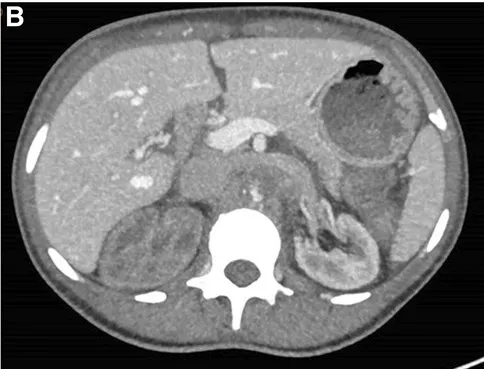

A TC também revelou importante circulação colateral na parede abdominal, permitindo suprimento sanguíneo suficiente para os membros inferiores. Apenas o rim esquerdo mostrou captação residual de contraste (Figura 1), sugerindo rim direito isquêmico.

TC com contraste (reconstrução 3D) mostrando oclusão aguda da aorta justa-superior da artéria mesentérica. (A) Oclusão aórtica justa-superior à artéria mesentérica (marcada com um ⊗) juntamente com vasos colaterais na parede abdominal (B) Rim esquerdo com realce de contraste e rim direito sem realce sugerindo falta de perfusão renal.